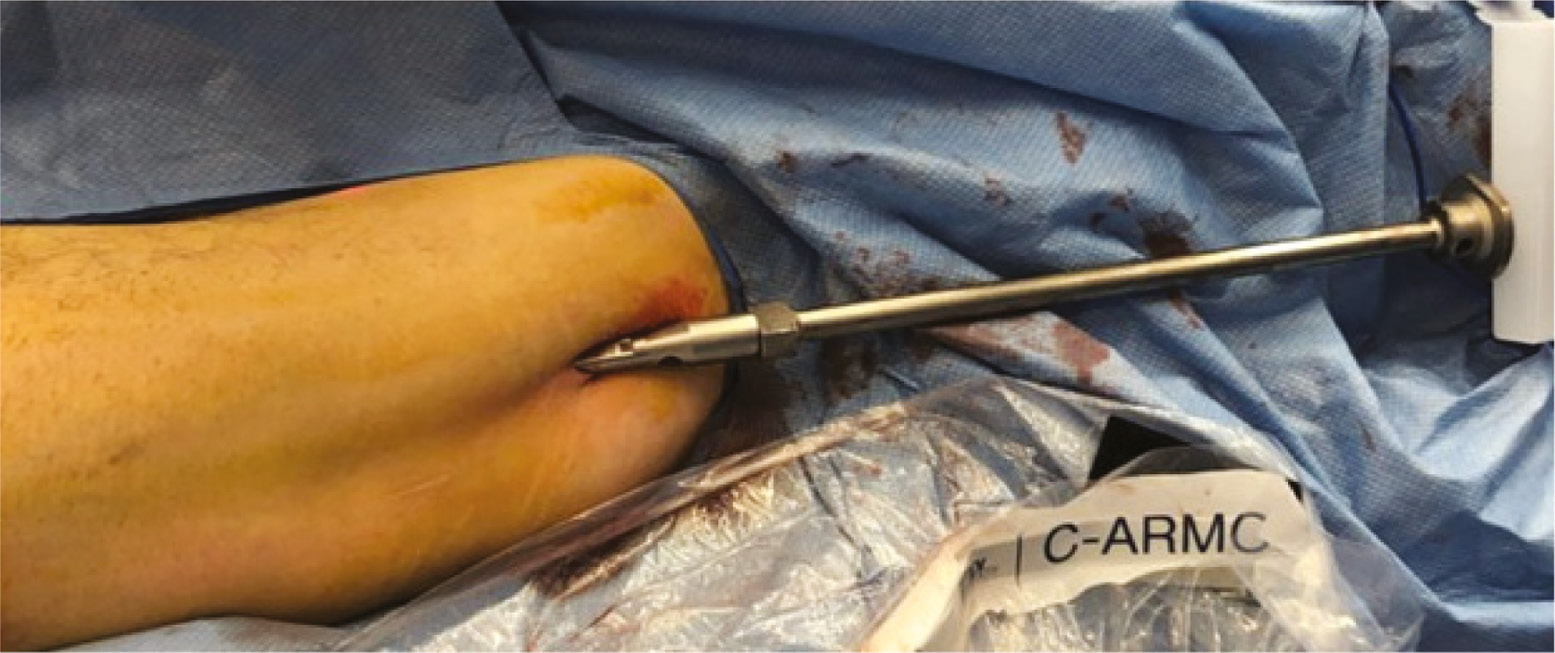

Figure 30. The hitting device cone insertion is placed over the wire.

jposna20220031_fig30.jpg

Figure 31. The hitting device for cone insertion is used to place the cone’s thick part close to the bone.

jposna20220031_fig31.jpg